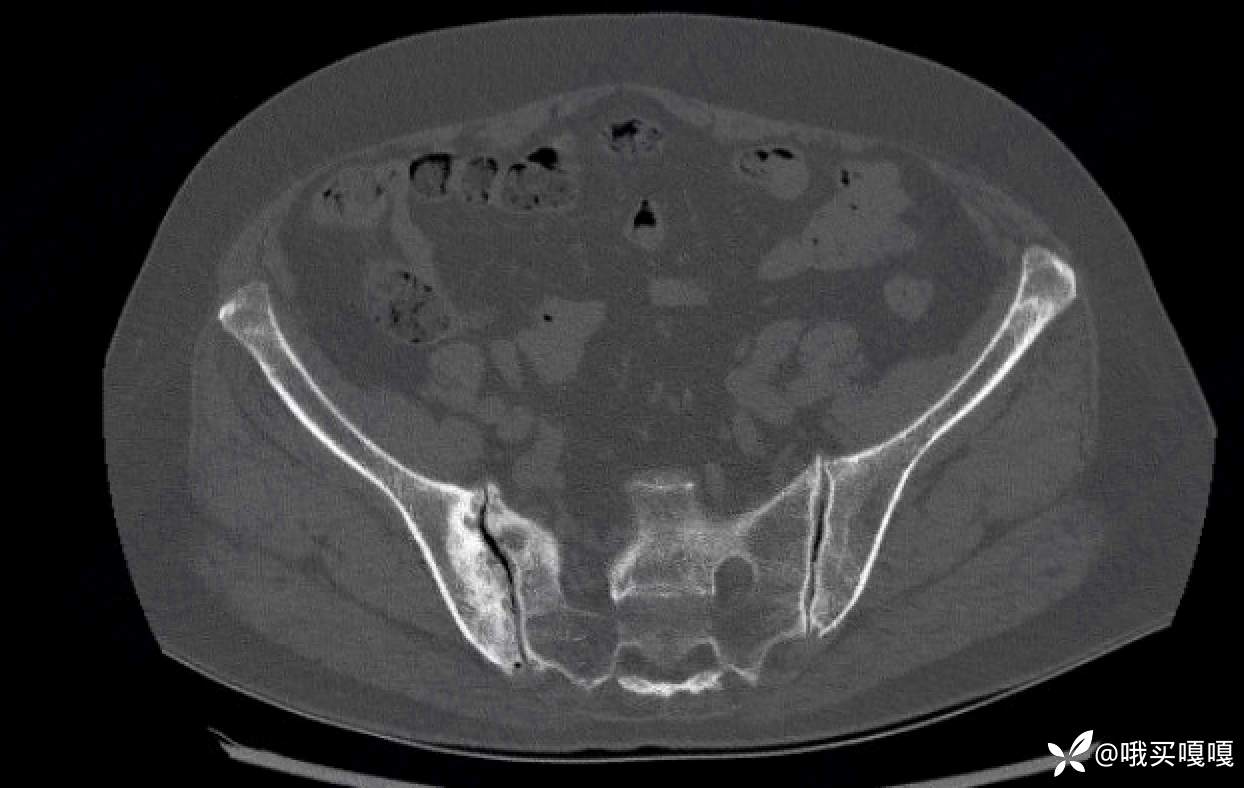

请问各位,这个骶髂关节的CT,看起来像脊柱关节炎引起骶髂关节炎的影像学改变吗?